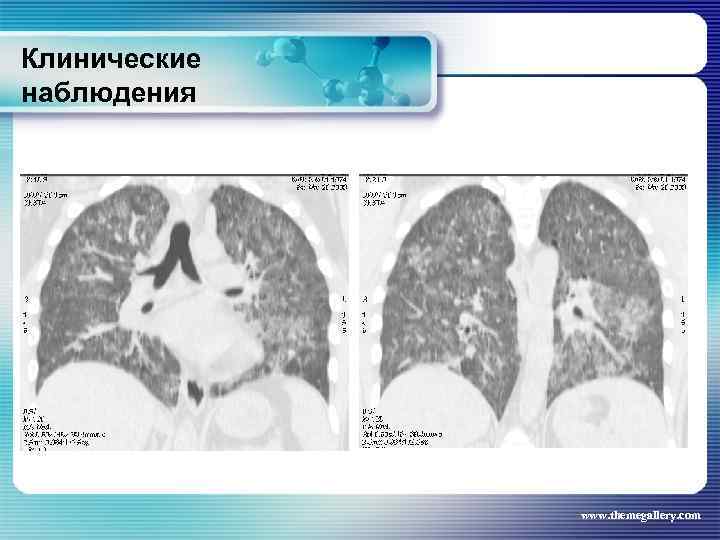

Клинические наблюдения Больной В. , 1974 г. р. Клинический диагноз: лимфома Ходжкина, нодулярный склероз IV В стадия с поражением подчелюстных, шейных, надключичных, подмышечных, паховых, абдоминальных, внутригрудных лимфатических узлов, легких, нижнегрудного и поясничного отделов позвоночника, костного мозга Проведено 8 циклов ВЕАСОРР, последний осложнился развитием тяжелого цитостатического пульмонита www. themegallery. com

Клинические наблюдения Больной В. , 1974 г. р. Клинический диагноз: лимфома Ходжкина, нодулярный склероз IV В стадия с поражением подчелюстных, шейных, надключичных, подмышечных, паховых, абдоминальных, внутригрудных лимфатических узлов, легких, нижнегрудного и поясничного отделов позвоночника, костного мозга Проведено 8 циклов ВЕАСОРР, последний осложнился развитием тяжелого цитостатического пульмонита www. themegallery. com

Клинические наблюдения Тот же пациент На фоне КГС терапии явления пульмонита купированы www. themegallery. com

Клинические наблюдения Тот же пациент На фоне КГС терапии явления пульмонита купированы www. themegallery. com